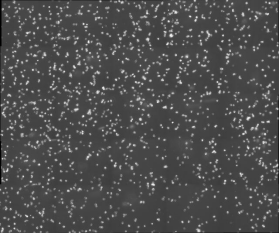

北京眼科研究所致力于探索眼科疾病的發(fā)病機(jī)制和治療方法,其中免疫學(xué)研究是其重要方向之一。在一項(xiàng)關(guān)于小鼠巨噬細(xì)胞的研究中,科研人員需要對(duì)細(xì)胞進(jìn)行長(zhǎng)時(shí)間的動(dòng)態(tài)監(jiān)測(cè),以觀察其在免疫反應(yīng)中的行為變化。然而,傳統(tǒng)的顯微鏡在長(zhǎng)時(shí)間成像時(shí)往往面臨成像速度慢、清晰度不足以及軟件操作復(fù)雜等問(wèn)題,這些問(wèn)題嚴(yán)重限制了研究的進(jìn)展。

MCS31配備了10XPH和20PH高分辨率物鏡,能夠提供清晰、細(xì)膩的細(xì)胞圖像,滿(mǎn)足基本的細(xì)胞成像需求。